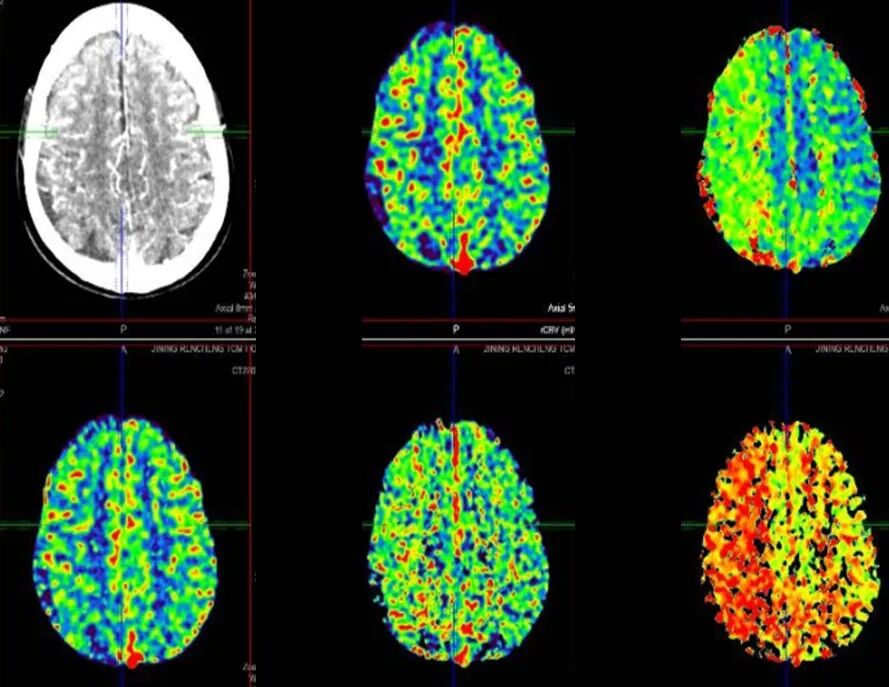

2022-7-20 颅脑CTP

重要影像结论:右侧放射冠区新发脑梗死,右侧颈内海绵窦段重度狭窄,右侧大脑半球缺血。

重要影像结论:右侧大脑半球缺血。